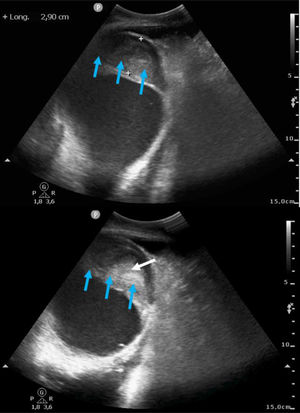

Presentamos el caso de una paciente de 61años con infarto de miocardio evolucionado hace un mes, que presentó complicaciones mecánicas postinfarto. La ecocardiografía evidenció un pseudoaneurisma apical de gran tamaño (fig. 1 y fig. 3: fecha azul) (Vídeo Anexo 1), con cuello de 2,93cm (fig. 1 y fig. 2: flecha amarilla) y paso de ecocontraste libre a su través (fig. 2: fecha roja), con la luz parcialmente trombosada (fig. 1 y fig. 3: fecha blanca). Se observó también un ventrículo izquierdo severamente dilatado y disfunción sistólica global muy severa (fig. 1) (FEVI 11%, IVT TSVI 7cm). A las 48horas de ingreso la paciente desarrolló shock cardiogénico SCAIC-D, que requirió soporte mecánico con ECMOV-A y balón de contrapulsación intraaórtico, logrando una notable mejoría de la perfusión orgánica. Tras coordinación con el hospital de referencia, fue trasplantada cardiaca código0, con una recuperación favorable. Este caso destaca la importancia del diagnóstico ecocardiográfico y el manejo con soporte mecánico en situaciones críticas de shock cardiogénico.